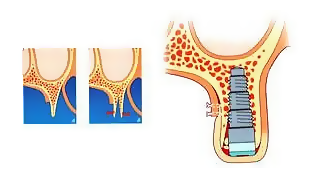

1. Якщо проводилося видалення зуба тривалий час назад і в області видаленого зуба, кісткова тканина розсмокталася (атрофировалась) і ясна над кістковим гребенем виглядає у вигляді тонкого вузького гребінця.

2. Імплантат має певну товщину в діаметрі. І при вузькому кістковому гребені (те місце між зубами, куди вставляється імплантат) його товщина може бути рівною або бути тонше діаметра імплантату. А після установки імплантату, між його тілом і краєм кісткової стінки з кожного боку має бути ще мінімум по 3 мм

3. Якщо не виконувати кісткову пластику перед установкою імплантата, то через короткий проміжок часу може статися оголення тіла імплантату та необхідність його раннього видалення (в цьому випадку йде втрата ще більшого обсягу кісткової тканини).